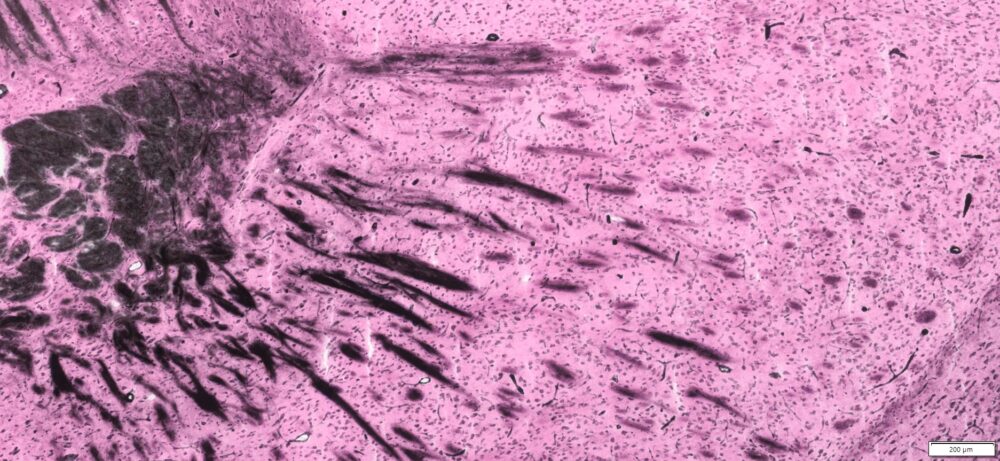

Expected Results

- Myelin and erythrocytes———–black

- Nuclei ———————————red

More Images